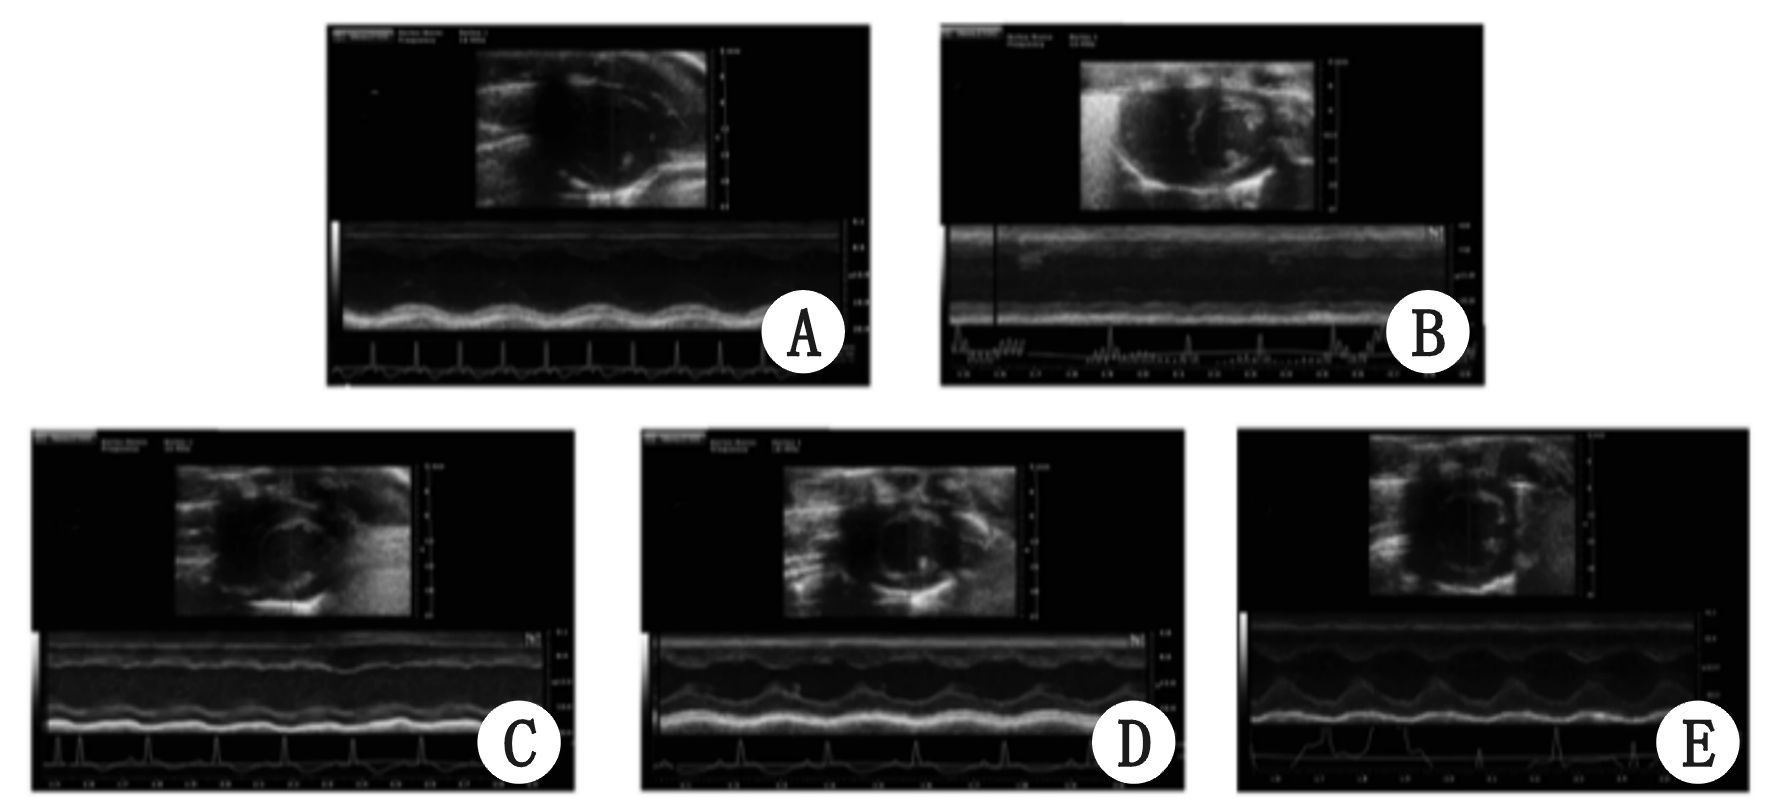

超声心动图结果示各组大鼠EF、MPI、IVSd和LVPWd等基线值的差异无统计学意义(均P>0.05) 。与Sham组比较,PR 4 h大鼠EF显著降低且MPI显著增高(均P<0.05) ,IVSd和LVPWd差异无统计学意义(均P>0.05) ;PR 12 h和24 h的EF值逐步恢复,但低于Sham组(P<0.05) ; PR 72 h与Sham组的EF差异无统计学意义(P>0.05) ;ROSC后各个时间点的MPI持续增高至PR 72 h(均P<0.05) ;PR 24 h和72 h的IVSd和LVPWd均高于Sham组(均P<0.05) ,见图 2和图 3。

| A:sham组 (n=3) ;B:PR 4 h组(n=8) ;C:PR 12 h组(n=7) ;D:PR 24 h组(n=6) ;E:PR 72 h组(n=5) 图 2 左心室乳头肌平面短轴M型及二维超声心动图 Figure 2 M mode and two-dimensional images from short-axis of left ventricle at papillary muscle level |